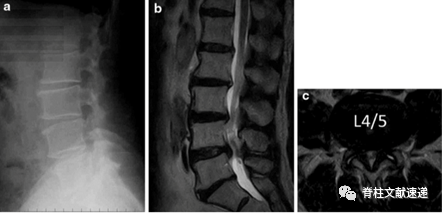

74岁男性,以间歇性跛行和左下肢坐骨神经痛1月为主诉就诊。查体未见皮肤病变,无肌力下降,无感觉障碍,无直肠膀胱障碍。MR提示L4/5椎管狭窄,如下图。

口服非甾体类抗炎药无效,2周内对其进行2次硬膜外封闭,效果欠佳,此时患者抱怨足面和足底水泡、破溃和红斑,且患者休息时疼痛症状无缓解。咨询皮肤科医生,诊断坐骨神经带状疱疹。给予抗病毒治疗1周后症状缓解。